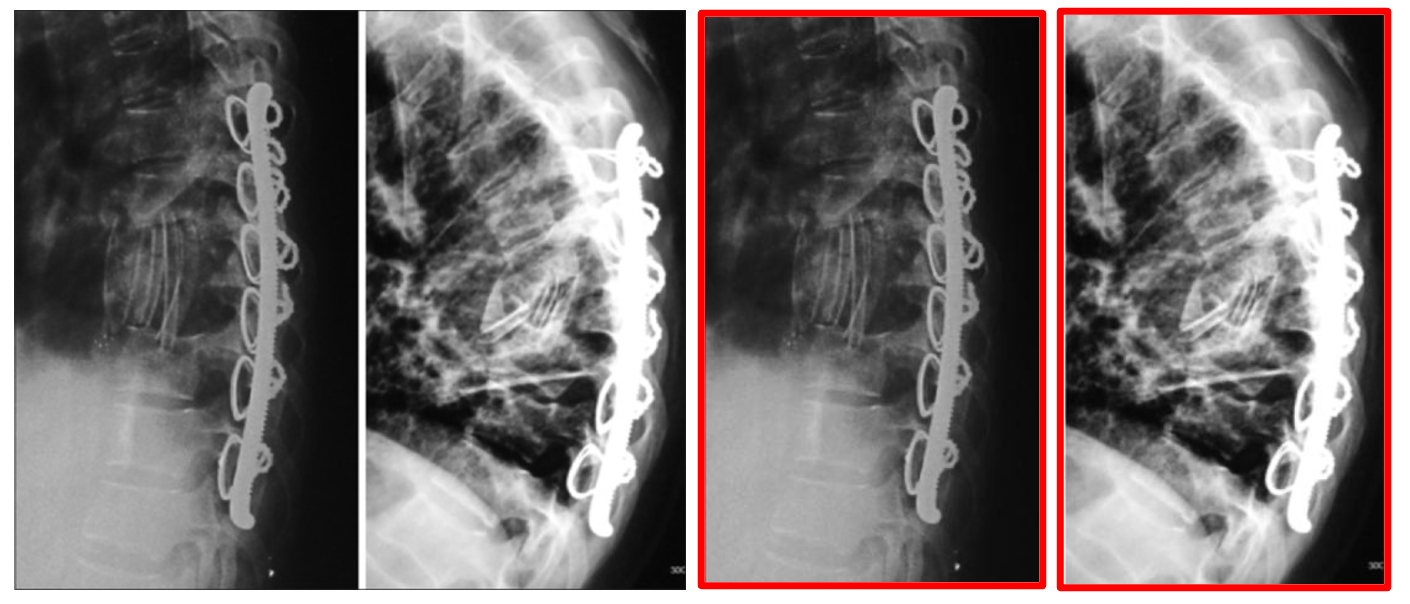

Articles: For scientific documents, we extract the figures as images. However, many of these figures contain multiple sub-figures, which can take nonconventional grid shapes and are labeled irregularly making the task of splitting into sub-figures and pairing with the correct sub-caption non-trivial. Since most compound figure layouts are not uniform and vary in the whitespace in between sub-figures, we train an object detection model based on the YOLO architecture [59] on sub-figure annotation datasets MedICaT and ImageCLEF 2016 [122, 38]. See more details in section 8.3 of the appendix including examples of non-trivial cases.

Articles: The majority of our curated PubMed data uses alphabetic labels in compound figures to denote sub-figures, which increases the complexity of pairing individual sub-figures from compound figures to sub-captions. Our solution leverages an optical character recognition (OCR) 111https://github.com/JaidedAI/EasyOCR on each sub-figure to detect the sub-figure labels, which we then match to the extracted sub-caption labels. To improve the reliability of this approach, we upscale the detected sub-figures by a factor of 4 to enlarge the sub-figure text label for OCR. We also impose a 95% confidence threshold on predicted text to isolate the sub-figure label, as text detected at lower confidence is often non-label text present in the figure (e.g. axis titles, graphs). We then attempt to match the detected sub-figure label with the sub-caption label. If a match is found, we pair the selected sub-figure and sub-caption. Despite the generality of this approach, we identified a few failure cases and proposed an error handling solution for these cases in section 8.5 of the appendix.